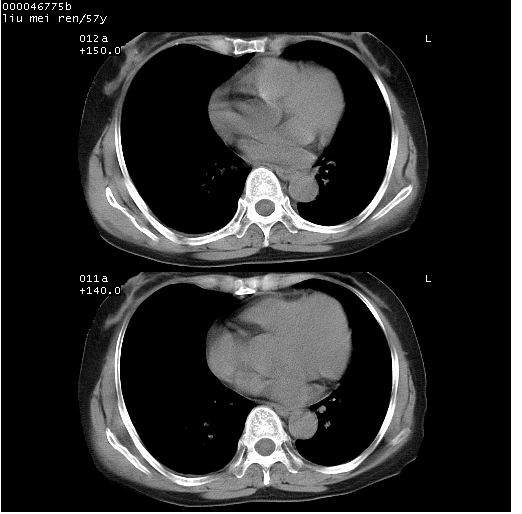

患者 女,57岁。因车祸受伤,其家属要求行“全身ct检查”。平素健康。

胸部ct轴位平扫(层厚10mm,螺距1.5,重建间隔10mm),图像如下:

左位上腔静脉,先天变异。

左位上腔静脉,先天变异。与双侧上腔静脉区别。